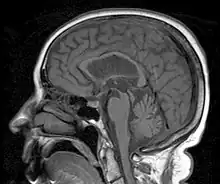

L'IRM cérébrale peut révéler quelques anomalies caractéristiques : amincissement de la partie supérieure de la protubérance (coupe sagittale), écartement des pédoncules cérébraux (coupe axiale), élargissement du 4e ventricule (coupe axiale), atrophie frontale.